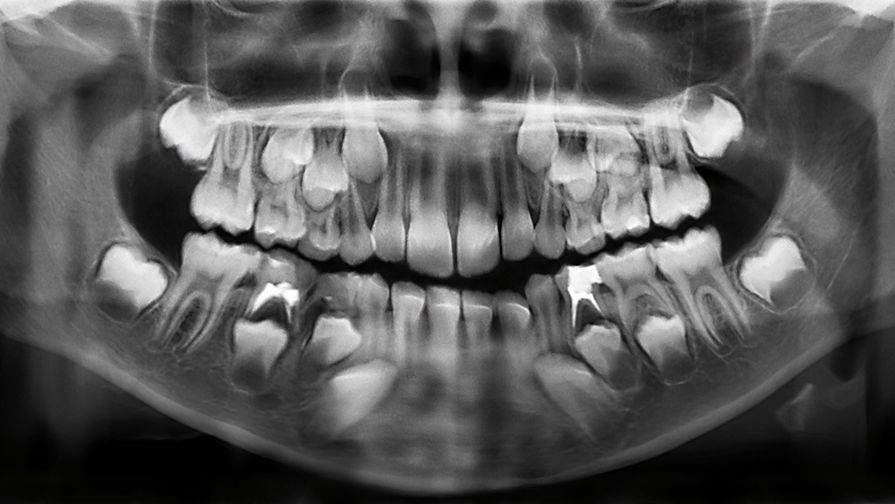

По молочным зубам можно выявить предрасположенность ребенка к психическим заболеваниям, выяснили американские психиатры. Они рассчитывают, что их открытие позволит надежно диагностировать возможные отклонения на ранних этапах.

По молочным зубам можно выявить предрасположенность детей к психическим заболеваниям, обнаружили специалисты из Массачусетской больницы. Исследование было представлено на встрече Американской ассоциации развития науки в Вашингтоне.

Исследователи работали с молочными зубами, выпавшими у шестилетних детей.

Ученые проанализировали зубы 37 детей старше шести лет. Они попросили родителей приносить им выпавшие молочные зубы и затем изучали толщину эмали, объем пульпы и другие показатели. Исследователям удалось установить взаимосвязь между характеристиками зубов и особенностями поведения детей, о которых сообщали родители и учителя.

Зубы начинают формироваться еще на этапе внутриутробного развития и, как поясняют исследователи, хранят информацию о том, что происходило с детьми во время беременности и в первые годы жизни.

«Зубы представляют собой многообещающий новый биомаркер, так как они хранят информацию не только о том или ином нашем жизненном опыте, но и о времени, в которое мы его пережили, — поясняют авторы работы. — Как годовые кольца на дереве связаны с его возрастом, так и изменения в зубах у детей связаны с психическими симптомами».